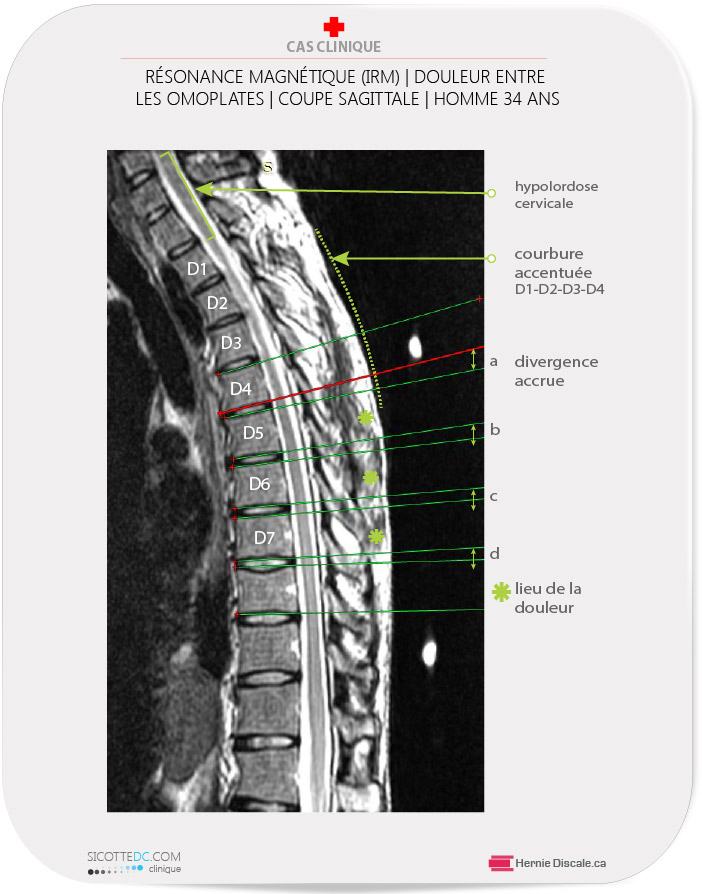

DOULEUR ENTRE LES OMOPLATES : CAUSE | DIVERGENCE VERTÉBRALE

Fréquemment, la douleur entre les omoplates est causée par une déformation des corps vertébraux de la région dorsale. L’IRM de la région dorsale ci-dessous démontre bien l’effet que peut avoir une mauvaise posture au fil des années. La différence entre la mesure du corps vertébral D7 ( 19,0 mm arrière, moins 14,1 mm avant ) démontre une diminution importante de la partie antérieure. Ceci cause une déformation cosmétique visible chez ce patient masculin de 45 ans.

Solution: Des soins en distraction Cox®, légères manipulations, modifications du style de vie et exercices.